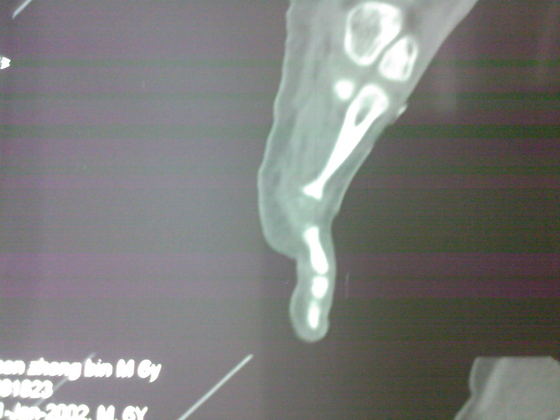

把病理送浙一医会诊后诊断为:骨外软骨瘤。同时做了CT检查。暂未予治疗。

今天把创面情况跟CT发上请大家看看。

继续发CT片